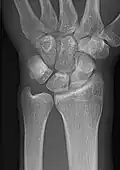

- Wrist - DP and Lateral

-

Left wrist by dorsoplantar projection -

Lateral projection